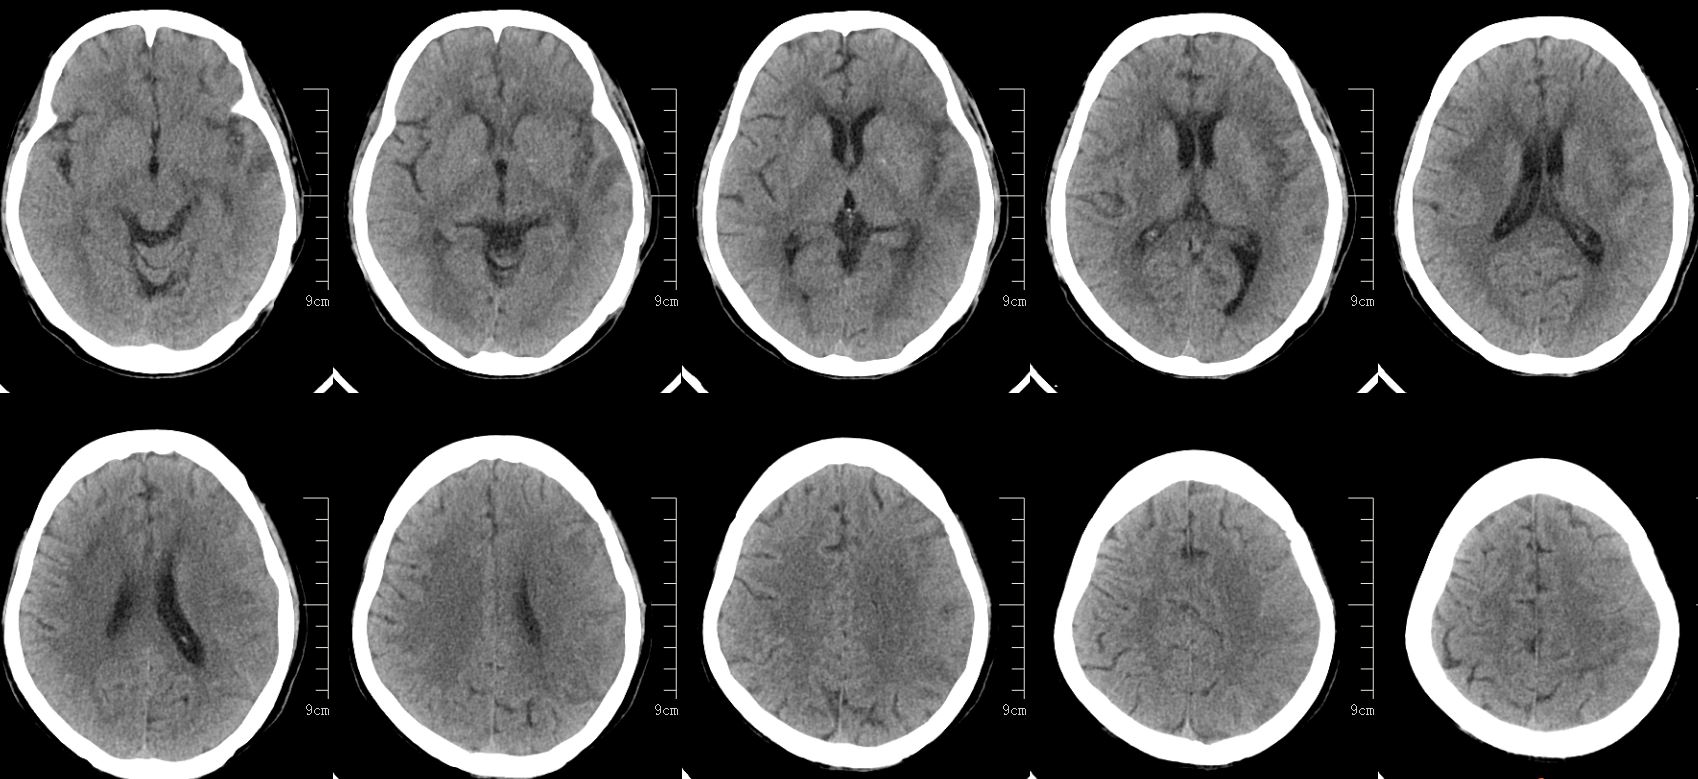

查体:神志昏睡、精神差、急性重症病容。GCS评分E2V3M5=10分,吐词不清,右侧口角、鼻唇沟变浅,示齿、伸舌不合作,双耳听力不合作,疼痛刺激能模糊定位,右侧肌力2级,左侧肌力5级,左侧病理征阴性。NIHSS评分:18分。ASPECT大脑中动脉评分2分。

进一步完善头颈部CTA检查,提示左侧颈内动脉闭塞。

虽CTA提示颅内段颈内动脉及左侧颈内动脉颅内分支无明显缺失,但大脑中动脉远端分支明显稀疏,显影不佳。再结合头颅磁共振了解代谢情况。

结合既往患者脑梗死行头颈部血管CTA提示双侧颈内动脉C4段重度狭窄,考虑此次发病左侧重度狭窄急性闭塞可能,对侧颈内动脉代偿不充分,和家属沟通,家属态度积极,理解病情,遂急诊手术治疗。